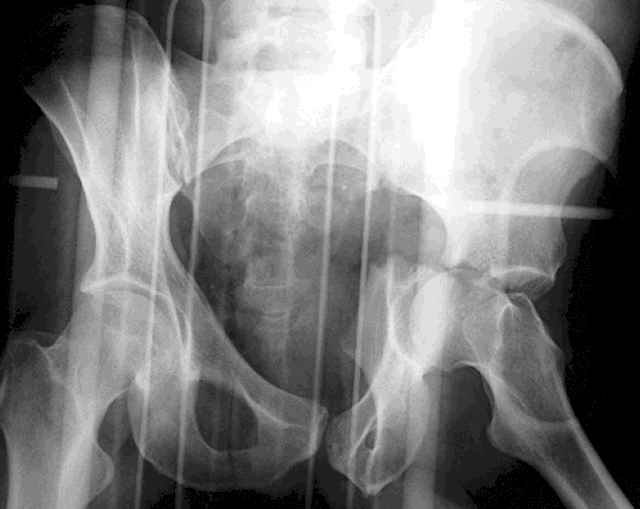

Screw Fixation

-AC Screw

-PC Screw

For Alex... here are some cannulated and 7mm screws for you... notice the fracture malreduction as indicated by the head subluxation on both views...this was a percutaneous technique without open reduction... I don¹t like it but there it is... the fixation technique is not at fault, because there was no open reduction of the fracture... but let¹s not get in to all that.